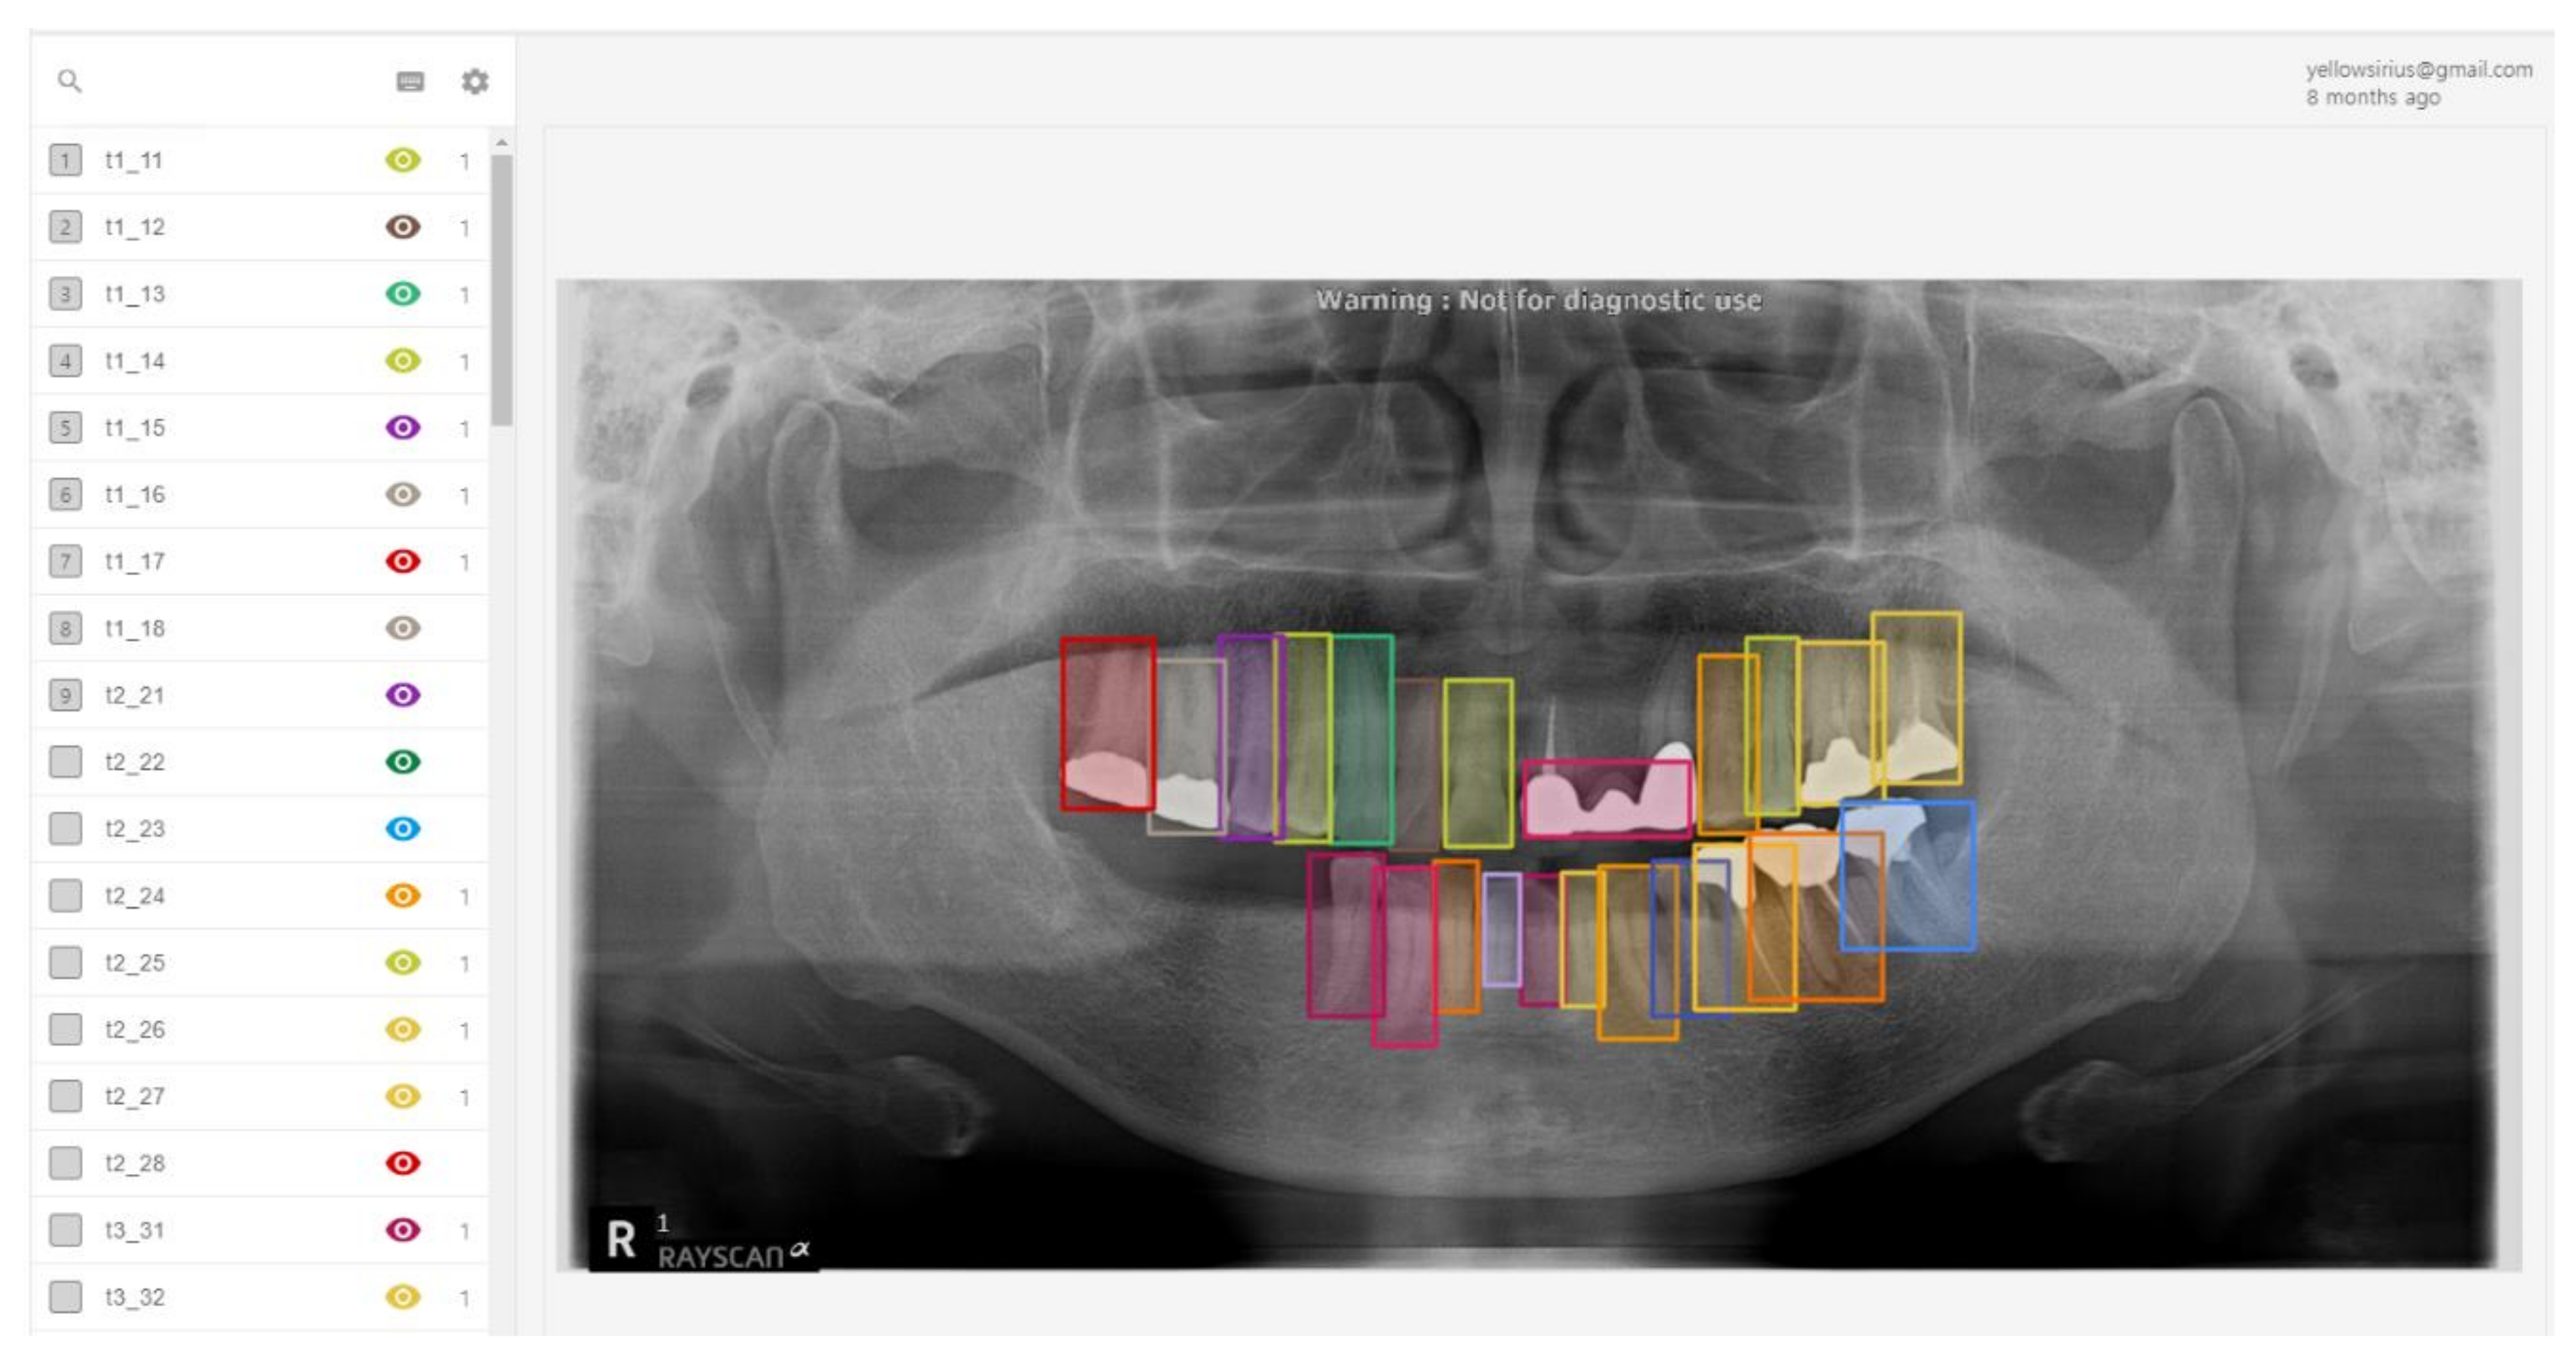

Table 3 shows that the probability of a tooth actually existing in the location indicated by the RCNN algorithm was 84.2%, with a sensitivity of 75.5%, and a precision of 84.5%. In addition, for tooth numbering, an accuracy of 77.4% was consistently obtained between the location of the actual tooth and the location indicated by the algorithms. The results of tooth detection are shown in Figure 10. As shown in this figure, all information about the position of the tooth can be detected correctly. However, it can be seen that the small tooth and crown cannot be detected for the tooth whose shape is not recognized.

Figure 10. Results of tooth detection.